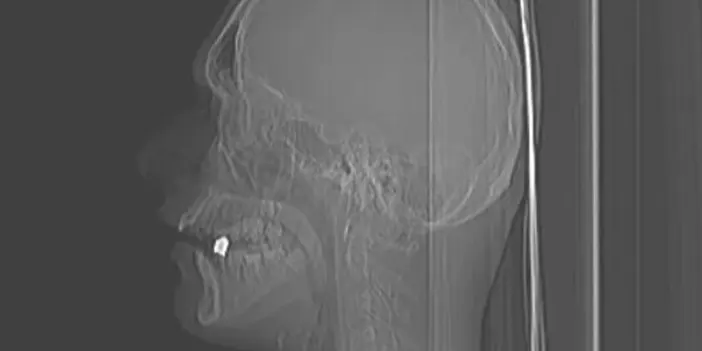

Kurşun 17 yaşındaki gencin boynundan girip ağzında kaldı. Ateş açan şüpheliler ise olay yerinden kaçarak uzaklaştı.

Kurşun Yazar’ın ensesinden girerek ağzında kaldı. Şans eseri hayatta kalan Aykan Yazar ihbar üzerine olay yerine gelen ambulans ile ekipleri ile hastaneye kaldırıldı.